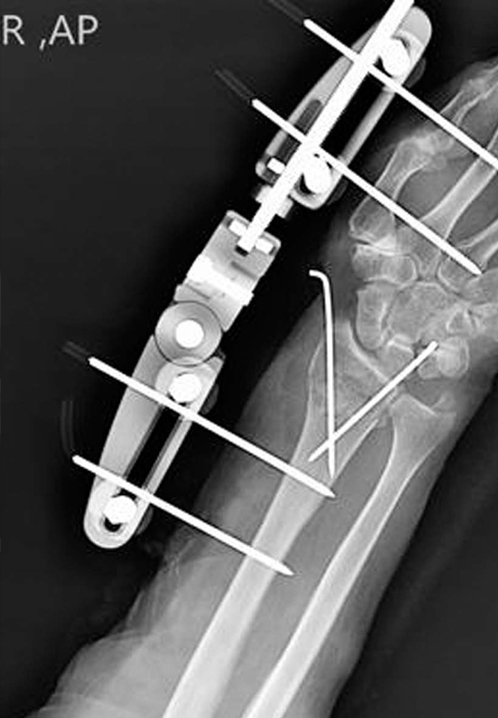

Dynamic Distal Radius

External Fixators

Concept

Distal radius fractures represent the most prevalent fracture type encountered in emergency settings. External fixation stands out as one of the optimal treatment modalities for managing distal radius fractures, particularly beneficial in cases involving articular or metaphyseal comminution.

Adjustment of the articular components of the external fixator is conducted in accordance with radiological parameters of the unaffected side.